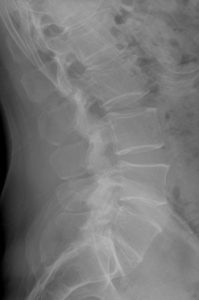

Our patient is a 35-year-old male with low back pain, accompanied by left lower extremity radicular symptoms.

We can see that the L5 vertebral segment is transitional with a broadened left transverse process that forms an anomalous articulation with the sacrum. The right transverse process is normal. The L5/S1 disc does not show signs of degeneration and is generally preserved, but the L4/5 disc level shows early degenerative signs such as spondylophyte formation. As will be discussed in the next section, this is a Castellvi type IIa lumbosacral transitional vertebrae.